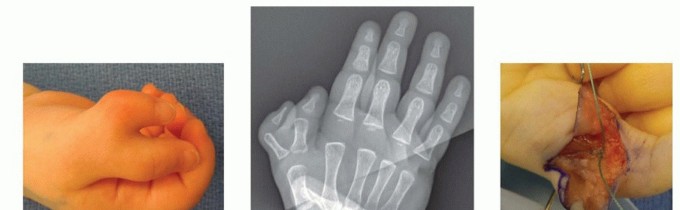

TECH FIG 2 • A. Clinical photograph demonstrating conjoined nails in a Wassel I thumb. B. Preoperative radiograph. C. Postoperative photograph demonstrates normal IP alignment and nail fold following resection of small duplicated thumb.

TECH FIG 5 • A,B. Preoperative photograph and radiography, respectively, of Wassel IV duplicate thumb. C. Intraoperative photograph depicting reinsertion of intrinsic musculature following deletion of radial duplicate thumb. D. Postoperative skin closure following deletion of radial duplicate thumb. The collateral ligament is reinserted, and the joint is tested for stability. The intrinsic musculature is reinserted (TECH FIG 5C).The flexor and extensor tendons are rebalanced.Skin is closed with 5-0 fast absorbing gut suture (TECH FIG 5D). Sterile dressings and a long-arm thumb spica cast are applied.Persistent jointangulation1. Failure to recognize deforming factors, such as misaligned tendons andresidual bony deformityPersistent jointinstability1. Collateral ligaments must be properly reinserted.Painful neuromas(see FIG 3)1. Digital nerves must be identified and cut short to retract away from theskin surface.